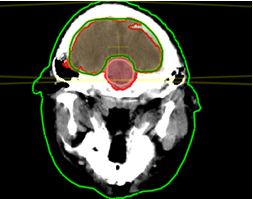

Lập kế hoạch xạ trị não và tủy bằng máy gia tốc cho bệnh nhân u nguyên bào tủy tại Trung tâm Y học hạt nhân và Ung bướu- Bệnh viện Bạch Mai

Bệnh nhân được điều trị bằng máy xạ trị gia tốc tạiTrung tâm YHHN và UB, Bệnh viện Bạch Mai

Bệnh nhân đã được phẫu thuật lấy u tối đa, sau đó xạ trị gia tốc toàn não và tủy 36Gy, xạ trị bổ trợ thêm vào diện u để đạt liều xạ trị tại u là 56,8Gy.